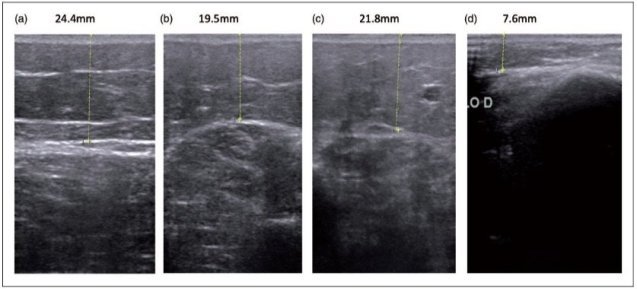

Lipödemde ultrasonografik değerlendirme

Lipödemde bacaklarda ödem sıvısı görülmez, ancak kalın yağ dokusu tabakası görülmektedir. Cilt dokusu ve kas arasındaki bölgede yeralan yağ dokusu ileri derecede kalınlaşır. Normal bireyler ile karşılaştırıldığında yaklaşık 2-3 misli yağ dokusu artışı saptanır.

Resim.Ultrasonda ciltaltı yağ dokusu kalınlığında artış